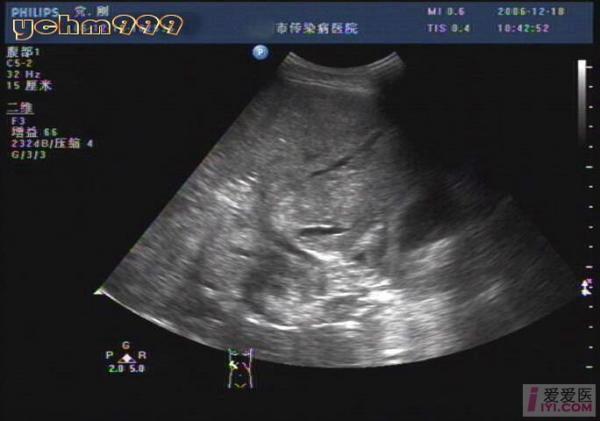

酒精性肝硬化伴肝ca,门脉血栓